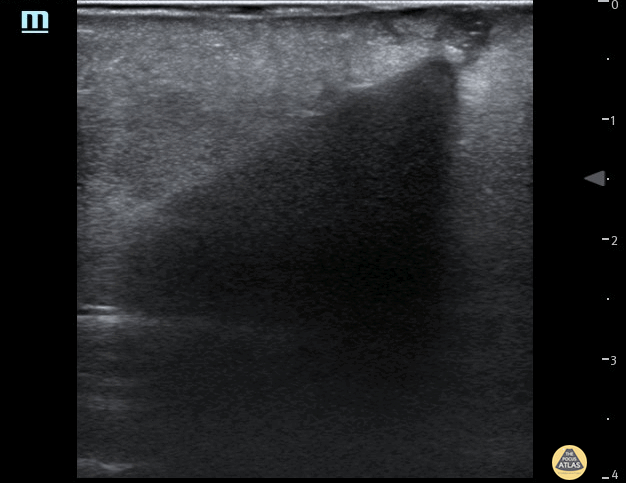

Soft Tissue - Foreign Body - Wooden Cocktail Stick

35 year female presented to the Emergncy Department with a self harm retained foreign body in the left forearm. The foreign body was a wooden cocktail stick not seen on x-ray. POCUS easily identified the cocktail stick by it's acoustic shadowing which allowed removal under local anaesthetic. Repeat POCUS scan showed no other foreign bodies. Dr Pete Hulme @Dr_Pete_EmMed